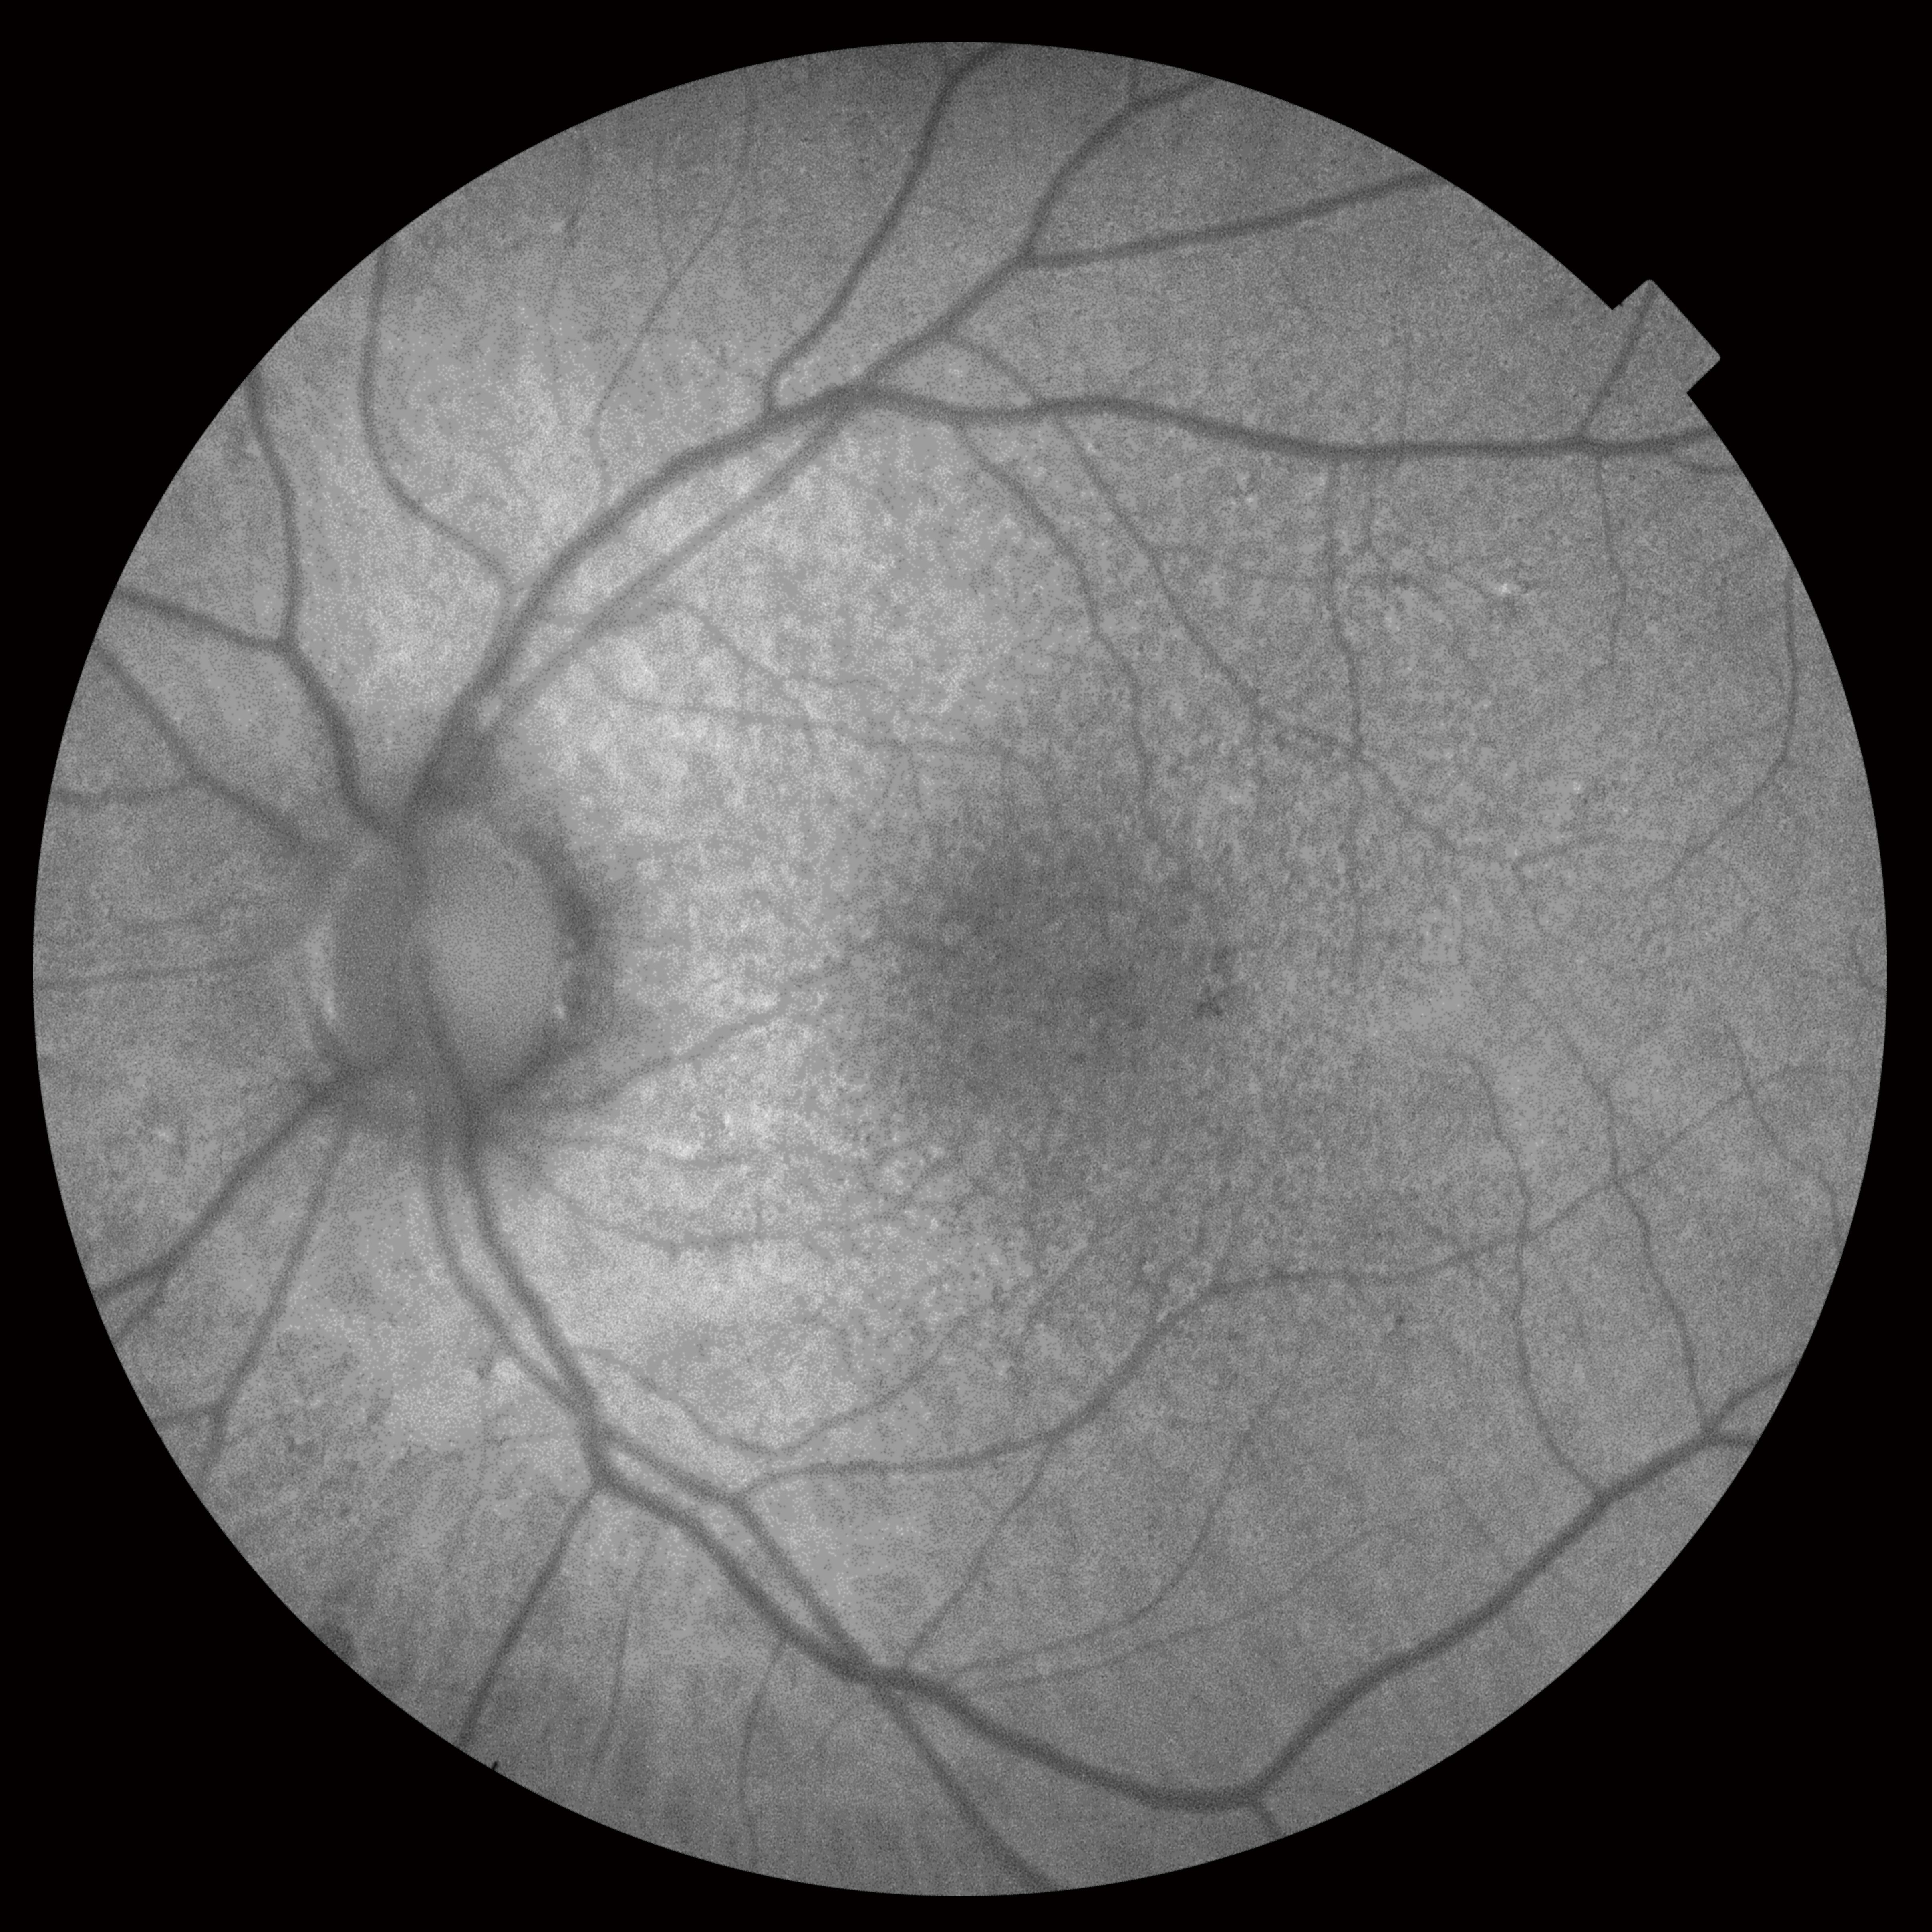

Уникальное сочетание нового механизма получения ОКТ-снимков SWEPT Source и сканирующего луча в инфракрасном диапазоне (1050 нм) позволяет получить качественный ОКТ снимок структур заднего отрезка глаза: стекловидного тела, сетчатки, хороидеи и склеры – на одном скане. Эта особенность сокращает время исследования за счет отказа от получения дополнительных снимков для получения снимков высокой четкости.

Большая проникающая способность инфракрасного излучения позволяет получить снимки даже в случае наличия помутнений в прозрачных средах глаза (катаракта, кровоизлияния и т.д.).

Помимо ОКТ и ОКТ-ангиографии прибор позволяет получить снимки глазного дна с помощью встроенной немидриатической фундус-камеры. Модель DRI TRITON plus оснащена также модулями флуоресцентной ангиографии (AF) и автофлуоресценции (FAF).

Уникальная система навигации позволяет определять локализацию каждого В-скана ОКТ на фундус-изображении и наоборот.